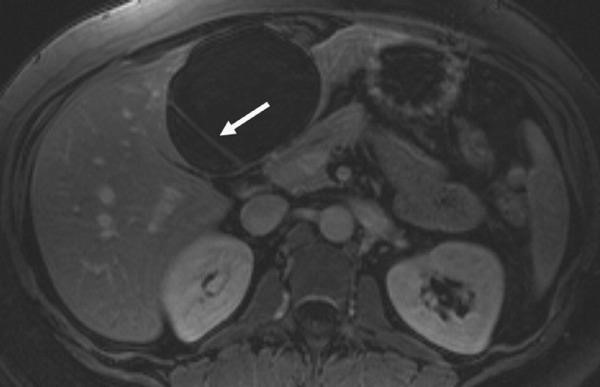

Simple cysts MRI

Complex cysts MRI